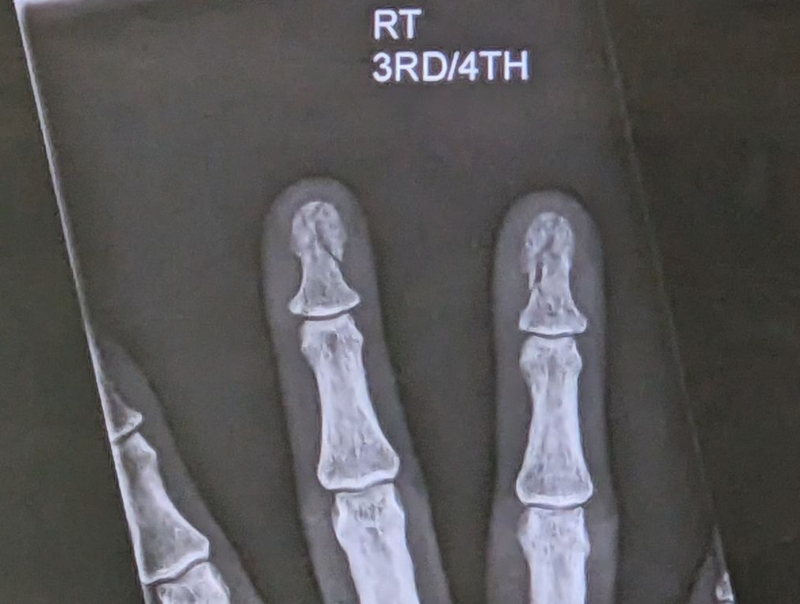

And the x-ray image is in. Just a few shattered fingertips, no big deal. At best, a month of healing.